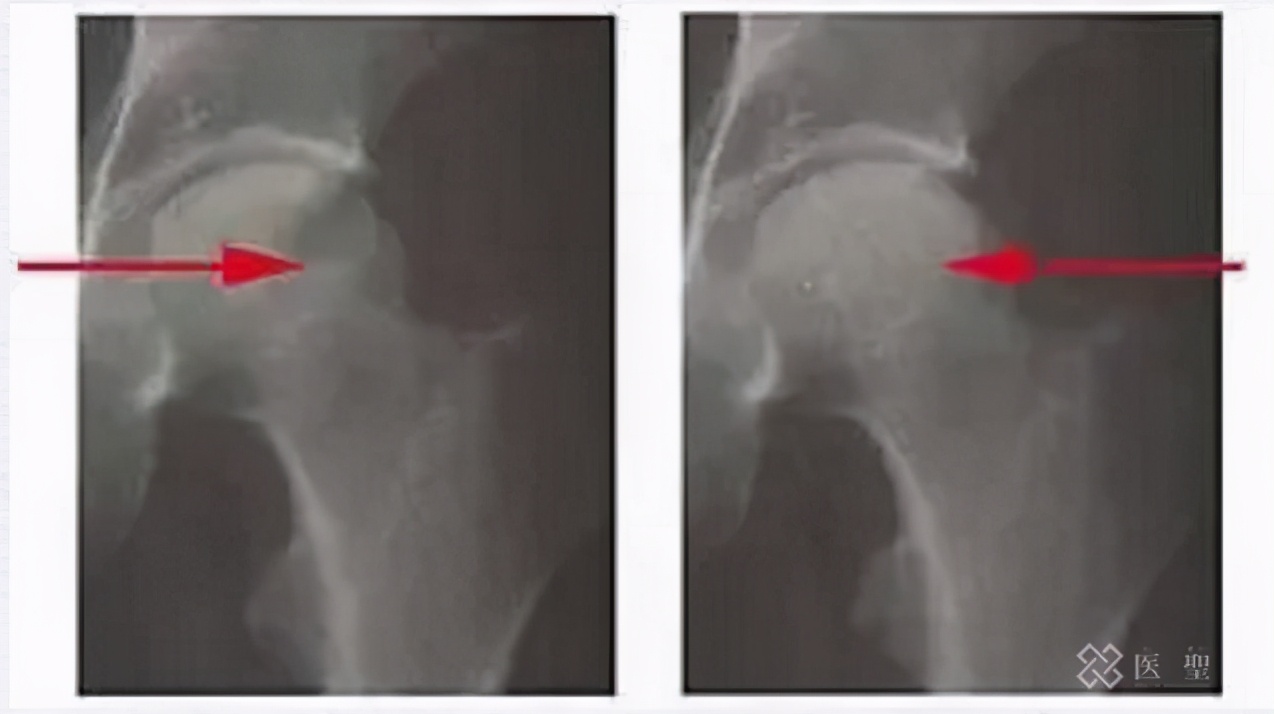

股骨头坏死的发病年龄主要集中在30 ~ 60岁,并且有年轻化的趋势。ONFH 因其早期临床症状不典型, 时常发生漏诊误诊, 大多数患者因此错过最佳治疗时机, 最终导致股骨头 变性 、关节疼痛、活动受限, 其高危害性给患者带来巨大的痛苦。

臀部疼痛、走路困难、腰痛、膝盖疼痛。